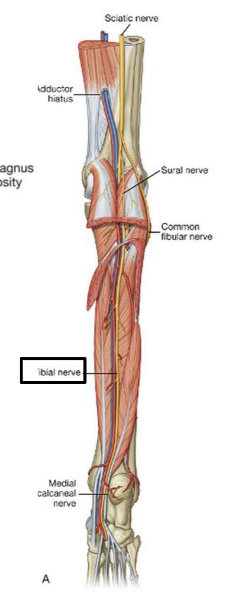

The sciatic nerve is formed from ventral rami from spinal cord levels ________-

L4 - S3

What is the path of the sciatic nerve?

exits the pelvis through the greater sciatic foramen. IN the posterior gluteal region, located inferior to piriformis m

Into which two nerves does the sciatic nerve bifurcate?

tibial and common fibular

The tibial nerve is fromed form ventral rami from spinal cord levels _______

L4-S3

The tibial nerve is the (medial/lateral) division of the sciatic nerve

medial

What is the pathway of the tibial nerve?

runs through popliteal fossa

runs with tom dick AN harry though medial malleoulus

bifurcates into medial and lateral plantar nerves

Which muscles are innervated by tibial nerve?

all posterior thigh muscles except short head of biceps femoris (long head, semitendinosis, semimembranosis)

^^technically tibial division of sciatic n

ALL posterior leg muscles (gastrocnemius, soleus, and plantaris. popliteus, tibialis posterior, flexor hallucis longus, flexor digitorum longus)

Into which nerves does tibial nerve bifurcate?

medial and lateral plantar nerve

origin course and distribution of sciatic nerve

O L4-S3

C leaves pelvis through greater sciatic foramen inferior to piriformis; enters gluteal region; descends deep to biceps femoris; bifurcates into tibial and common fibular nerves at apex of popliteal fossa

D no muscles

origin and distribution of tibial nerve

O sciatic nerve

C forms as sciatic nerve bifurcates at apex of popliteal fossa; descends through popliteal fossa; runs inferior to tibialis posterior with posterior tibial vessels; terminates beneath flexor retinaculum by dividing into medial and lateral plantar nerves

D supplies plantar flexor muscles of the posterior compartment of the leg and knee joint